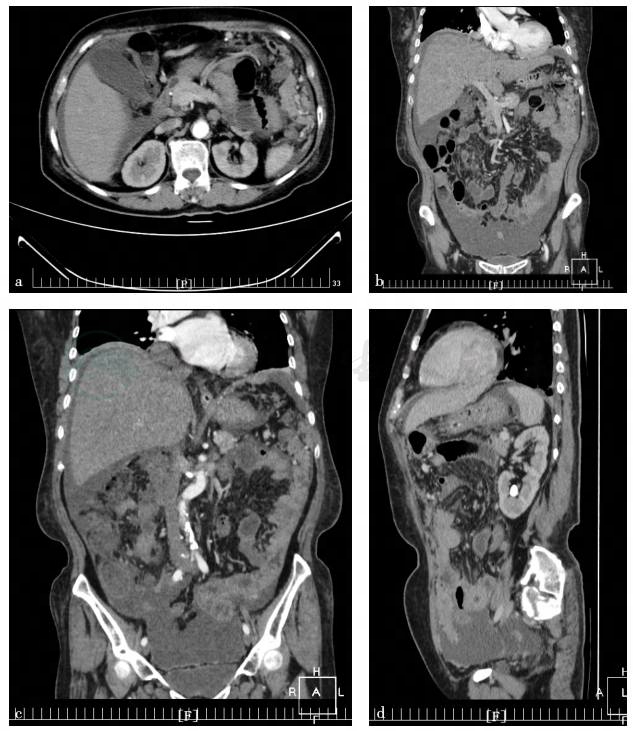

图1 腹部立位X线片

a. 2017年11月28日:中腹部小肠管内积气;b. 2017年12月17日:肠梗阻改变

现病史:患者于1个月余前开始出现持续性腹部胀痛,阵发性加重,可放射至背部,伴恶心、呕吐(进食即吐,呕吐胃内容物,无呕血及呕咖啡样物),肛门停止排气、排便。患者自诉无畏寒、发热、身目黄染,病程中无黑便。外院腹部X线立位片:考虑不全性肠梗阻,左肾结石。患者于外院经抗炎补液(具体不详)处理,症状缓解不明显,近5天未排便,肛门排气减少,遂来我院诊治。

患者为老年女性,出现不明原因肠梗阻,伴有腹水、发热、贫血,考虑为消耗性疾病。经相关检查,明确腹水为渗出液,非血性腹水,此时需考虑如下可能。